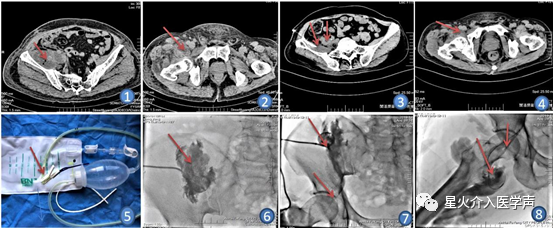

入院查体:体温:36.9℃,脉搏:88次/分,呼吸:18次/分,血压:101/70mmHg(1mmHg=0.133 kPa)。腹部体检无明显阳性体征。右侧下腹部靠近腹股沟区局部皮肤红肿、皮温增高,压痛(+),右侧腹股沟浅表淋巴结可触及肿大,右侧髋关节活动受限。辅助检查:急诊血常规:白细胞计数13.82×109/L,中性粒细胞百分比91%。盆腔CT平扫:右侧盆腔脓肿(图1,2)结合患者病史、体征及辅助检查,临床诊断:右侧盆腔脓肿、化脓性阑尾炎术后、高血压。[岁1]

入院后完善相关检查,在数字减影血管造影下行盆腔脓肿穿刺引流术,术前阅读盆腔CT定位右侧盆腔脓肿大致解剖位置,于右侧髂前上棘下方2cm平腰4椎体水平与为穿刺点,局麻后穿刺脓肿成功,经穿刺针注入造影剂造影示:[2] 右侧髂窝见一巨大脓腔,大小约10cm×5cm×4cm(图6),未见脓液累及股管。术中置入引流管,引流管外接引流袋。术后常规穿刺脓液常规细菌培养及药敏试验选择敏感抗生素、脓腔定期冲洗、保持负压引流管通畅等对症支持治疗。一周后右腹股沟出现一6cm×4cm大小溃疡面,基底部红。急查血常规:白细胞计数20.06×109/L,中性粒细胞比80.9%。盆腔部CT:右侧盆腔脓肿仍有,引流管在位(图3,4)及盆腔MRI:右侧髂腰肌、腰大肌及股臀部软组织脓肿形成(图A-I)[岁3] 。结合患者盆腔脓肿引流欠佳,遂再次行脓肿穿刺引流术,术中经原引流管造影示:右侧盆腔脓肿与右侧股脓腔经股管相通(图6,7),术中经股管置入6F引流管,引流管远端送至右侧股脓肿脓腔远端,术后股脓肿引流管外接负压引流球及引流袋组合装置(山东贝诺斯医疗器械,图5)。所引流脓液行细菌培养和药敏试验,根据脓液药敏结果选择敏感抗生素抗感染。[岁4] 每日先用250 mL生理盐水经引流管反复冲洗股脓肿及回抽脓腔液至体外,直至回抽纵液体清亮时结束。再注入25mL庆大霉素与生理盐水混合液冲洗脓腔,保留30分钟后连接负压球持续引流。每间隔4-6天复查盆腔CT观察脓腔面积缩小程度及引流管远端位置,必要时在DSA下逐步外撤调整引流管位置,保持引流管末端位于尚未闭锁的脓腔下极为最佳[1]。患者15天复查盆腔部CT:股脓肿明显吸收,透视下将引流管拔出至体外,三月后门诊随访患者恢复良好。

图①介入前盆腔CT:右侧髂棘前脓肿(箭头所指为脓肿);图②介入前盆腔CT:右侧髂腰肌脓肿?(箭头所指为脓肿);图③第二次介入前盆腔CT:右侧髂棘前脓肿及引流管位置(箭头所指为引流管及脓肿位置) ;图④第二次介入前盆腔CT:右侧髂腰肌脓肿(箭头所指为脓肿位置) ;图⑤第二次介入所使用的十字型引流管及负压装置 (箭头所指为“十字形”);图⑥第一次介入造影观察脓肿大小及形态;图⑦第二次介入造影盆腔脓液可通过股管与大腿脓肿相通(箭头所指为引流管及股管位置) ;图⑧第二次介入经股管置入导丝及盆腔脓肿经股管流向股软组织(箭头所指为导丝及股管位置)。[岁2]